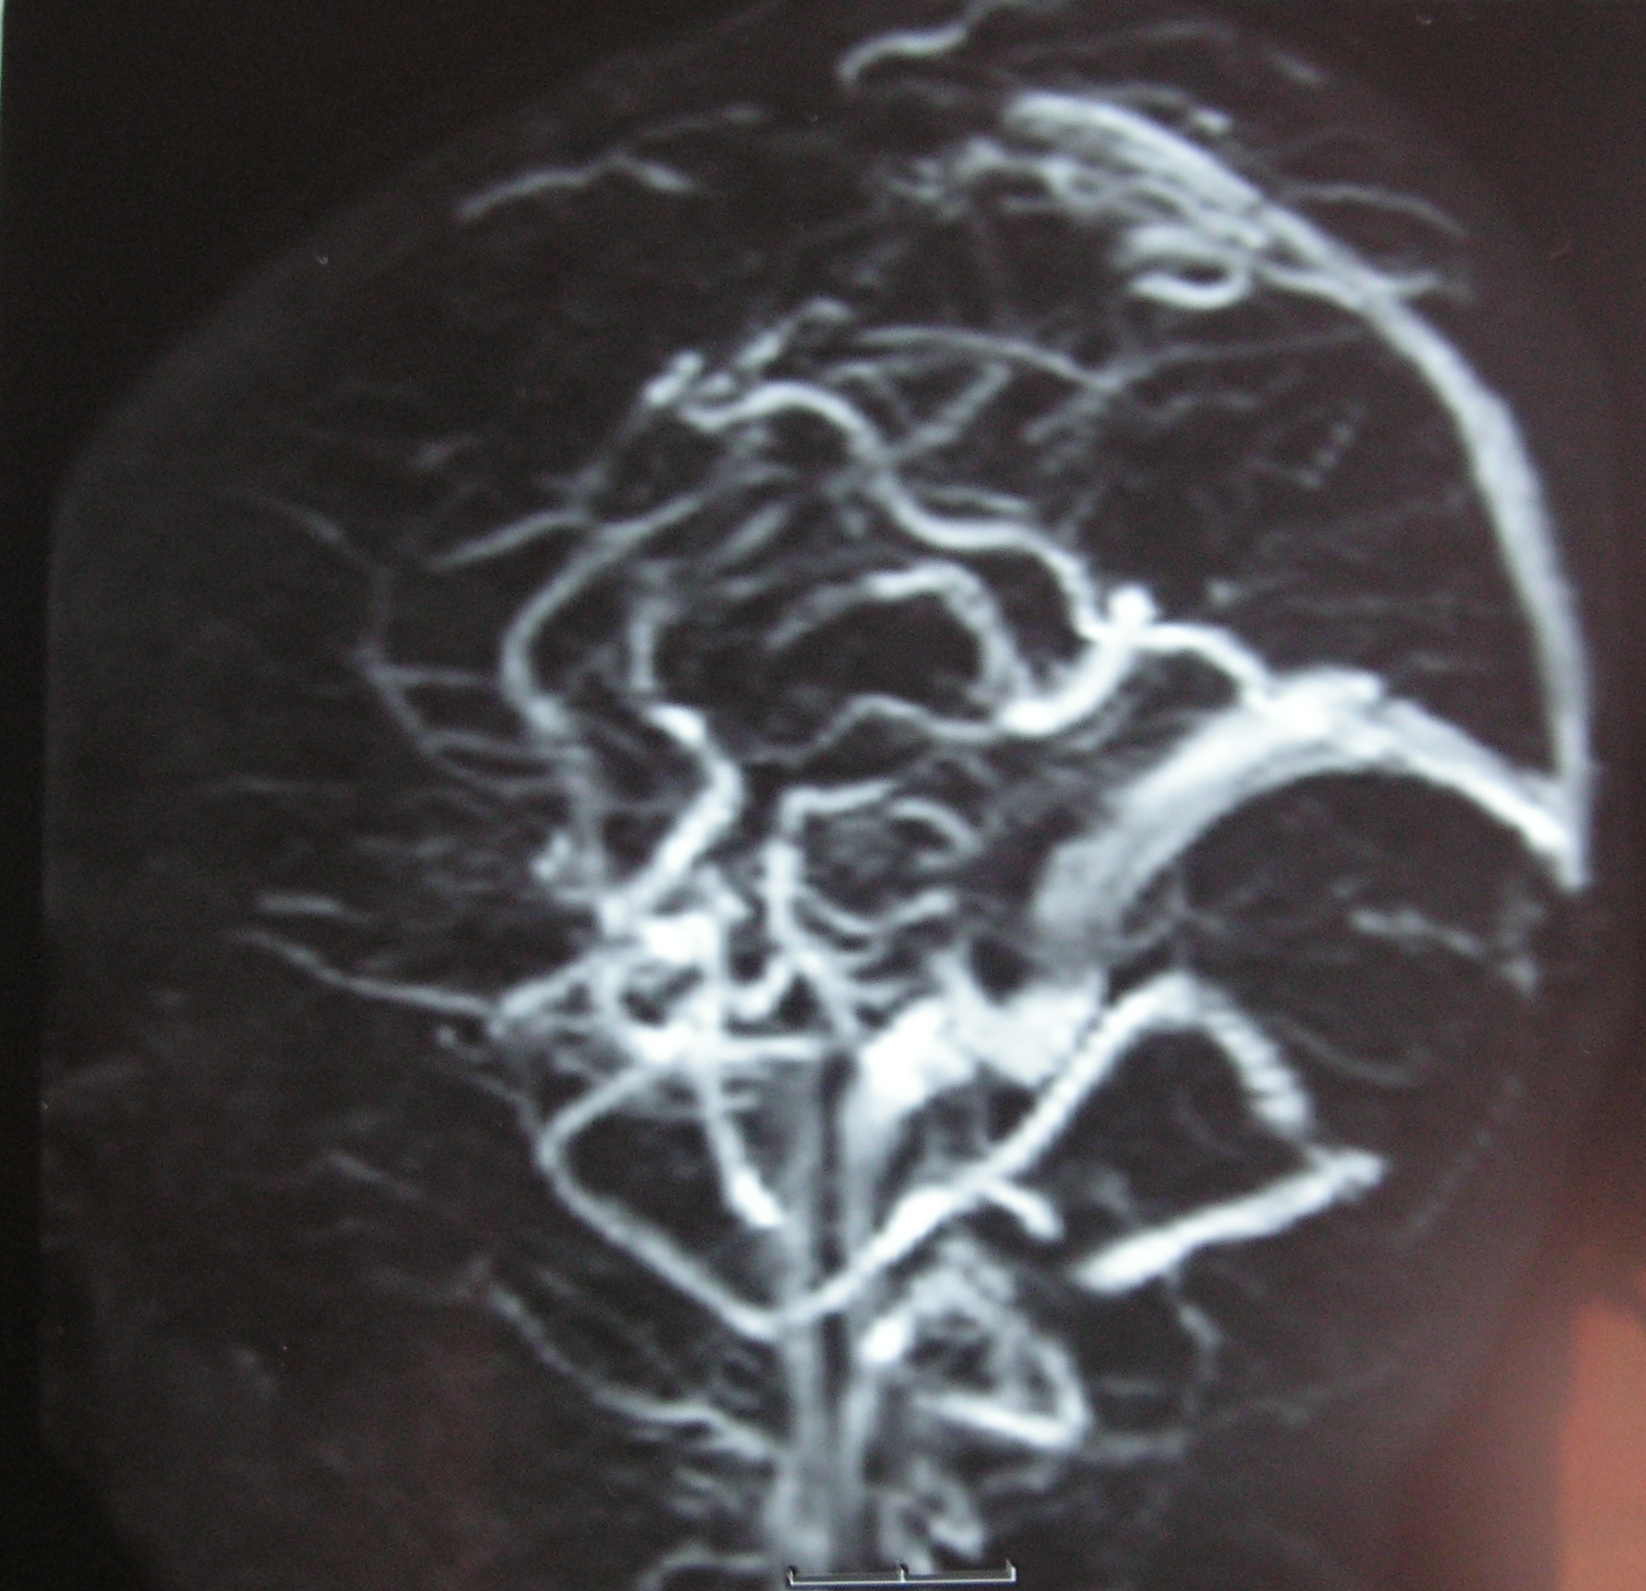

Beyin atardamarları (Arteryel inme) ya da toplardamarlarında (Sino-venöz inme) tıkanma olabilir.

Bir çocukta ani felç, motor kayıp geliştiğinde zaman geçirmeden çocuk acil ünitesine başvurulmalıdır. Beyin ve beyin dammar görüntüleme incelemeleri ile teşhis konulur, uygun tedavi uygulanır, altta yatan sebep araştırılır.